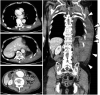

Displaced rib fractures can injure intercostal vessels leading to chest wall hematomas. As the bleeding occurs within the vessel, compression of the vessel wall helps in preventing further bleeding. Therefore, chest wall hematomas rarely result in shock. A thin 78-year-old man transferred to the emergency department with complaints of left dorsal pain due to an injury. He had a history of hypertension and aorta dissection. He arrived at the ED in a state of shock and presented with a large left dorsal wall mass. Subsequent imaging using computed tomography angiography revealed a large hyperdense hematoma at the left dorsal-flank wall along with rib fracture (11th intercostal artery). Moreover, a large fusiform aneurysm was detected from the abdominal aorta to the iliac arteries. Extravasation of the contrast agent was detected at the branch of the 11th intercostal artery, and hence, embolization was performed. The dermis, which comprises collagen and elastin fibers, plays an important role in vessel compression to prevent bleeding. The aortic media also comprises collagen and elastin fibers. Cell turnover, loss of collagen, and excessive elastolysis are associated with the formation of abdominal aortic aneurysms. The systemic degeneration of connecting tissue (collagen and elastin fiber) appears to be progress in patients with an aortic aneurysms and history of aortic dissection compared with other healthy older individuals. Physicians should be cognizant of the potential unexpected large hematoma complications if a risk of systemic connecting tissue degradation exists, as seen in patients with aortic aneurysm or aortic dissection.